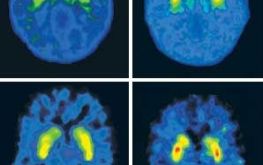

Dr. Nora Volkow on Marijuana

Dr. Volcow is one of the world leaders in research on addiction.